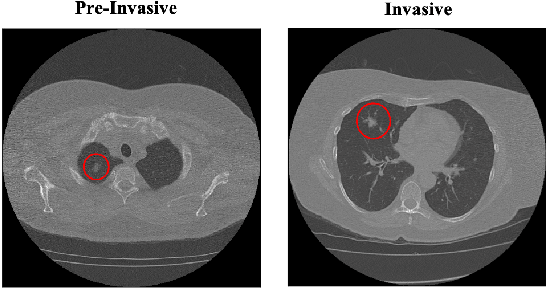

Abstract:The paper proposes a novel hybrid discovery Radiomics framework that simultaneously integrates temporal and spatial features extracted from non-thin chest Computed Tomography (CT) slices to predict Lung Adenocarcinoma (LUAC) malignancy with minimum expert involvement. Lung cancer is the leading cause of mortality from cancer worldwide and has various histologic types, among which LUAC has recently been the most prevalent. LUACs are classified as pre-invasive, minimally invasive, and invasive adenocarcinomas. Timely and accurate knowledge of the lung nodules malignancy leads to a proper treatment plan and reduces the risk of unnecessary or late surgeries. Currently, chest CT scan is the primary imaging modality to assess and predict the invasiveness of LUACs. However, the radiologists' analysis based on CT images is subjective and suffers from a low accuracy compared to the ground truth pathological reviews provided after surgical resections. The proposed hybrid framework, referred to as the CAET-SWin, consists of two parallel paths: (i) The Convolutional Auto-Encoder (CAE) Transformer path that extracts and captures informative features related to inter-slice relations via a modified Transformer architecture, and; (ii) The Shifted Window (SWin) Transformer path, which is a hierarchical vision transformer that extracts nodules' related spatial features from a volumetric CT scan. Extracted temporal (from the CAET-path) and spatial (from the Swin path) are then fused through a fusion path to classify LUACs. Experimental results on our in-house dataset of 114 pathologically proven Sub-Solid Nodules (SSNs) demonstrate that the CAET-SWin significantly improves reliability of the invasiveness prediction task while achieving an accuracy of 82.65%, sensitivity of 83.66%, and specificity of 81.66% using 10-fold cross-validation.

Abstract:Lung cancer is the leading cause of mortality from cancer worldwide and has various histologic types, among which Lung Adenocarcinoma (LAUC) has recently been the most prevalent. Lung adenocarcinomas are classified as pre-invasive, minimally invasive, and invasive adenocarcinomas. Timely and accurate knowledge of the invasiveness of lung nodules leads to a proper treatment plan and reduces the risk of unnecessary or late surgeries. Currently, the primary imaging modality to assess and predict the invasiveness of LAUCs is the chest CT. The results based on CT images, however, are subjective and suffer from a low accuracy compared to the ground truth pathological reviews provided after surgical resections. In this paper, a predictive transformer-based framework, referred to as the "CAE-Transformer", is developed to classify LAUCs. The CAE-Transformer utilizes a Convolutional Auto-Encoder (CAE) to automatically extract informative features from CT slices, which are then fed to a modified transformer model to capture global inter-slice relations. Experimental results on our in-house dataset of 114 pathologically proven Sub-Solid Nodules (SSNs) demonstrate the superiority of the CAE-Transformer over the histogram/radiomics-based models and its deep learning-based counterparts, achieving an accuracy of 87.73%, sensitivity of 88.67%, specificity of 86.33%, and AUC of 0.913, using a 10-fold cross-validation.